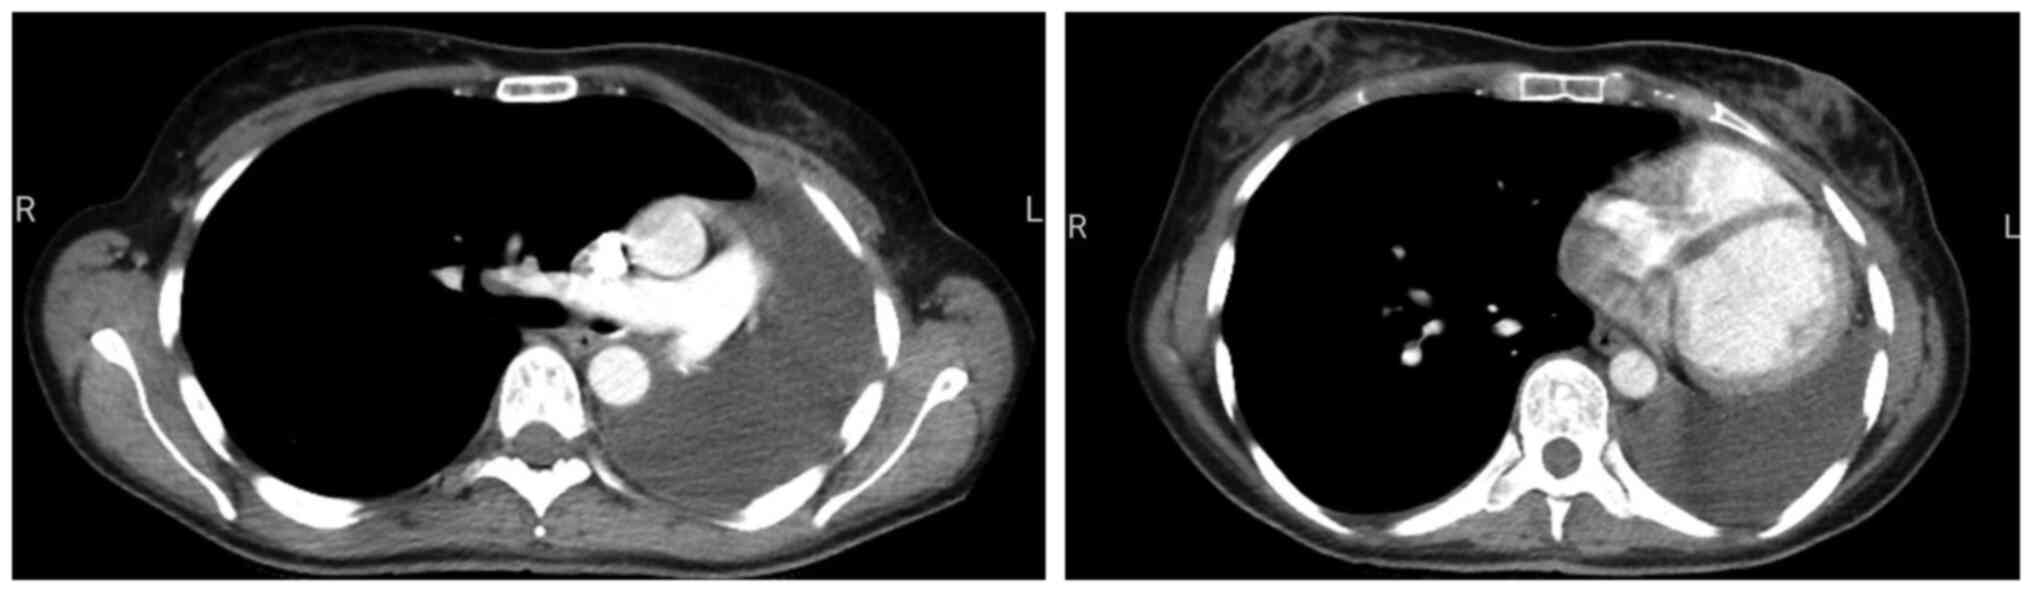

As it is the only type of pulmonary resection that leaves the entire pleural cavity empty, specific changes are expected after pneumonectomy. Typically, after surgery, the empty space is filled with air, which is then gradually replaced by fluid. Then, in a course of 1-7 months (2), the pleural cavity should be entirely obliterated. Obviously, these changes also have an anatomic impact, such as the rise of the diaphragm and the shift of the mediastinum towards the empty cavity, also narrowing the intercostal spaces on the same side (Fig. 1).

Figure 1

Normal post-pneumonectomy aspect-CT scan at 2 months after left pneumonectomy for cancer using video-assisted thoracic surgery, for a central typical carcinoid with lung destruction after one year of evolution, in a 23-year-old female patient-section at the level of the great vessels (left) and at the level of the heart ventricles (right).

After pneumonectomy, given an uneventful post-operative course, effusion in the post-pneumonectomy space usually accumulates ex vacuo as pleural pressure equilibrates to zero (18). The fluid builds up gradually in weeks to months as the air resorbs partially or totally, as exemplified in Fig. 1. As this happens, the mediastinum is still shifted to the operated site but when an abnormal level of fluid rapidly accumulates or air is present, the mediastinum is pushed to the contralateral side, the heart is compressed and the patient usually has a certain form of cardiovascular and respiratory symptomatology (tachycardia, hypotension, high venous pressure, tachypnoea, marked dyspnoea at rest, cardiac tamponade, pericarditis).